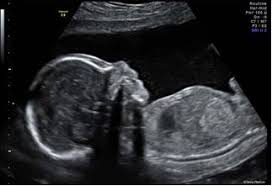

48+ Anatomy Scan Down Syndrome Ultrasound Signs. Antenatal screening of down syndrome (and other less common aneuploidies) should be available as a routine component of antenatal care. The diagnostic value of a detailed first trimester anomaly scan in fetuses with increased.

Ultrasound scan codes and indications for a full list of the current codes for claiming for ultrasound scans through the new zealand public health * note: Down syndrome is associated with a host of distinctive physical characteristics, medical issues, and technically speaking, parents and doctors look for signs of down syndrome, rather than on an ultrasound (an image of a developing fetus, also called a sonogram), visible signs a baby may have. Normal anatomy of the abdomen, scanned in the portal venous phase. Progressive ossification of the posterior elements of the vertebrae hinders satisfactory examinations in.